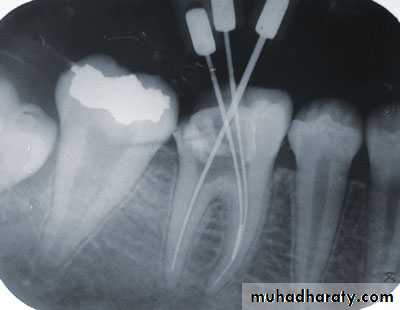

Separated Instruments

Recognition

• Removal of shortened file from the canal• Loss of original working length

• Radiograph is essential for confirmation

There are three approaches:Attempt to remove the instrument using:

• Small file to bypass the instrument• Removal by ultrasonic device

• Using especially designed pliers